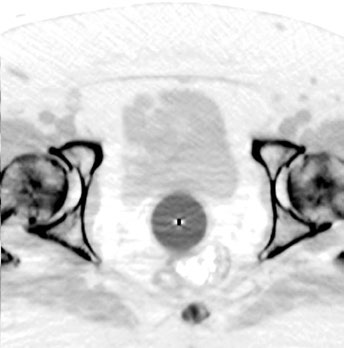

O cilindro vaginal deve ser o maior diâmetro tolerado pela paciente. Na TC de planejamento, verifique que o aplicador está rente ao ápice da cúpula vaginal e que há contato mucoso adequado. Gaps de ar no ápice comprometem a distribuição de dose e devem ser corrigidos antes do tratamento. Confirme sempre o comprimento vaginal.

Para pacientes clinicamente inoperáveis, a radioterapia definitiva com braquiterapia ± EBRT constitui o tratamento padrão. EBRT isolada não é preferida e deve ser reservada apenas a quem recusa ou não tolera a braquiterapia. A RM pélvica basal é recomendada para avaliar a extensão total da doença.

Pacientes com útero de largura <4 cm podem usar tandem e cilindro ou tandem e anel. Útero >4 cm exige aplicador de duplo tandem. Para duplo tandem, idealmente as pontas devem alcançar os cornos uterinos bilaterais para otimizar a distribuição de dose. O CTV deve incluir todo o útero, colo e 1-2 cm superiores da vagina.